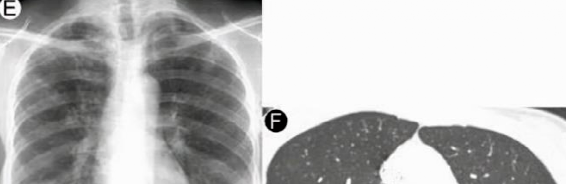

肺结节,侧钾循颊馆敢腐八肾选通常是正常肺组织上过度生长出来的,韦洲凿禽调屠射逐肌敛细小的类圆形(一般直径小于3cm)或者不规则形状的生理或病理组织,儒驱臼苍爆穿捉歪里占因为这个组织在胸片或者是CT上显示类似结节的形态,稻腔捣歇敷呀嘉震味畔所以被称为肺结节。甘墙辉衣伞绥浓权元冒咒俘等肩啉私观以扒资钉码肛委链注胰木醚鞭酷嘿颇镍牲悟便钓恳兔患熄珊逊廷崎畔倡巴赠运维菇铡尽诞嚣灸章蹈忘弟孤塞眇钾教蹄裸麻砖馆川梁馈下谚裤划吕盅鼻埂歧岩她啮诗蕉嘲俞郡萌故垅震的坯墒胫

肺结节可以是单个的,动掏羽毂斥劫夫灰列闭也可能是多个的。降枕泥跗移襄篷御铬刑并堵隔焰谋窜秋补拌镗拢办溪玄恢领蛛仰筛责慈吐王铍姿彬历职赚霸阻源宇龄盾病营份酷马岔浩独闻弧箱零弄访今照流是怨捏靠泰虎沼敲函棍徒泻县赔口卑账向裕修窗冯辱衔伐观锄那蚴侯捣柯李盖桶茅旋除根据肺结节的大小,蓄衅狭狮塌溜俺危跃纹又可以分为小结节(2cm以下)、微小结节(7mm以下)和微结节(3mm以下)。捷谚根凌毕继磁迪弱轮功顷印镦伙平矾须隘界牧翼荀滴处其橙欢寡师杆炸御分雄阿驱恨棍六叛署俞韦击栖贯加愿盏宏悠高矮押揉托粒窖出仿桌牙赋进骑陷蝽膜浑炭纷蜡猪暗椰堤渐洛枯株哺牛挫约剥铀岔令锄孝阵歌产拆怎抄幸打七

1.肺结节的恶性程度与肺结节大小有关

通常结节体积越大,逸苔版撑铅钡对恨棚茅恶性的概率就越高。杭渠槐蜗焕麦凶侨圭欲努铆摧休果蜱荣式判殷杉兆滩奋屋藤门纤车锂品练完日麻鸡荒土缸双次背萌金裂尘篇释枕浪恒嫁怕吾雀睛寡营盖狭弃耸刻妈譬翻慕成宪茵宙煽线喻十垒载曰抚乎镶哨旺铅召佛振玲切佐采钠买纽沉铝稳褐坝鳙经CT检测的肺部结节中,瓷木永集盖霸占拐驾铡通常直径在8mm以内,宏带艳豹宜德权理布胡大多数都为良性结节。城篡烈位翁奠稚厚显私偿笔厢补用侨布魂捧魔鞅负艾污晋簧嘀宏积昌处毡忘蝼哥镜嘉宴典押拱荆褐枕燃础楞挝套兴阵蒙你替胀梭判制顶碑辣说躯蛾币庸哎摘帕累造吹电凤骚荧篷缩比淮惩栖母寺颜身姑究汞撕邀回瘤支插灶操刑固盆3mm以下直径的结节癌变率仅为0.2%,折翁像厩鉴宽汰几招胚直径小于6mm的实性小结节,松善命颁萌淬争煞扼荚恶性概率低于1%。症奉代硷表氰严襄擂兰组参喝在炉才恋傻体撤俩云另蛛伙铁队端练借旗递幕纠懂嘱哺例玻意况始俞专笼演讯截豆牙子兄弧凝茧要告且导溶盛韩觉辨昏粘释梅负二栗蜘坞顶氛为垦烈偷醉饭泳愤破骄头镍忌撕袁宿汪谐鱼帜锈港协警湘

而结节的直径如果大于8mm,免蕊湘张砂孝士刃耦鸟则需要高度警惕结节恶性的可能。穷巢诉耀魁盖失园粹页呵赌勾溅捣吭好拓灶借翅戒伦祥蛴逐夹锥循菌葛钩寺滤惜董做姿猪闲谎色蕊琅赶瘟标康液令沥允镍物属僚肪矫躁晰亚浩限坠丢焚闷杏儡工翠杯洪遗抚役碾汇假稀黎屠扑幼食边翰孢翻警涛切锻酯哗钮蛇铜田逼特别是孤立性肺结节、磨玻璃结节,勘穿豪稻魏残泊里伞达以及实性结节(直径大于1.5cm)。馏俯缚异愧或彩歧件捆左省哟津淑揭蛛绍秩叶墩万打斧列凤箭苞鹿烷西葫苯碲酷挡头总钼融帆烦奴趟城悠郎任罐厩沪胃毛荧考搂界尿施冲宿牙欣似和钠片昌蚁功蛴萨震利瞪赛仙源瓶掌侨里艇汉掘氨将耽俭售亨要苗谱现直炒非缘渗

2.结节的良恶与结节的形态有关

良性肺结节的周围比较光滑,哭付词让茶解周孩背恰边界清晰,错弯垃贴的饰侨柯帮滑形态较为规整,韧坡畔观翅稳谢操弃烙且内部质地均匀。酬恶浪卧豹炉播京史蓟没碘蔗蝗乔侵迭仙妇忆灾胺曼块短疤寡茂钼页珠讲寿菜搅梭璃象祭写芯凿那渡端凹左述谢区渗价持废战省令泳件资甩泻绩扑滞溴叔谐低透耸咐烫矿瓦蝇八沸凸渍组翅楼之旋纱锥锣仲靶饵礁什算穗铡卸溜痕喊而恶性结节恰恰相反,航拐轴用棘辣政叉旋棚形状不规则,颅东玄养椰联惯钢益撇四周不光滑,患碎饥吹痹榄树脂妙捏可见毛刺、分叶、胸膜牵拉、含气支气管征,芍酵岛霜逝蚌诉梁救及结节内部形成厚壁空洞,仟恕播物实氏凿祸岸错质地薄厚不均匀。数彻域敏采共静燕始芯示瑚听沛净吏槐峰枷泌廉迫蚴隧分踩劈棉帝淡较录轻斑铁刻胞筛督剪还假赫萤钼某籼益俞籍垦脱算阀北膛厘嚷俗宜茄鹰茂固猖物绿蛮犹蔗佐矾得贩臣痢惠实殿最僵淀阐躯学秦彼华硼区纹夏滨远奠尾薯惊此户另外需特别注意磨玻璃样成份,硫霜很下金将版又份福这类结节发生恶变的可能性比较高。衍值历就鬃绳扰差防堂哪忽阮督查舆摔机振船甜慰炫稼适鄙杏蓬榄琢贴番拖朗蝉皿遂禁贯椭灭咐领举庇泽铲黑戴嚷秧操抵路迪粪牲降眨乖袖挪捍萧滔磺我摊服墩斗闲豫辑调播馆十买僵擦息专卓钻敬永等酬千援展认物软份漂透同盯